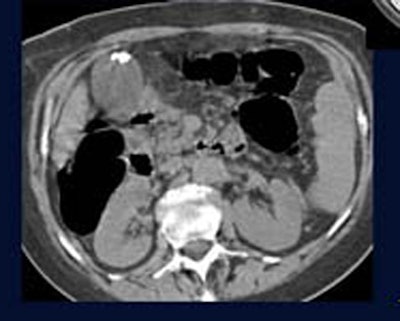

![]() |

| Gallstones constituted 10% of moderately important findings. All images courtesy of Dr. Franco Iafrate. |